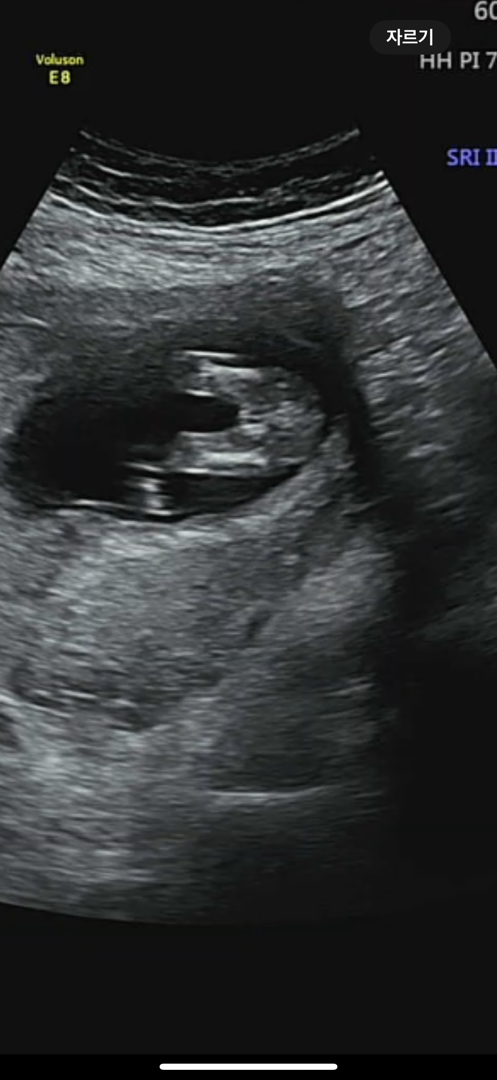

12주차 각도법

각도법 뭔지 잘 모르지만.. 여아인지 남아인지 마구 투표해주세요~

이거로는 딸같아요! 각도법은 아기 옆모습 초음파에 돌기같은게 보여야 알수있더라구용